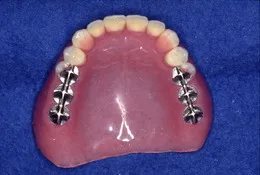

精度の良い金属フレームを採用しています。当院では日本の金属フレーム製作のパイオニアである川島哲氏が製作したものを使用しています。精度が不十分なものは再製作していますので安心しておまかせ下さい。

(金属フレームの入れ歯は薄くて強度があるためお口の中での異物感をあまり感じません。)

(まさに『匠の技』が活かされた金属フレームの部分入れ歯です。)